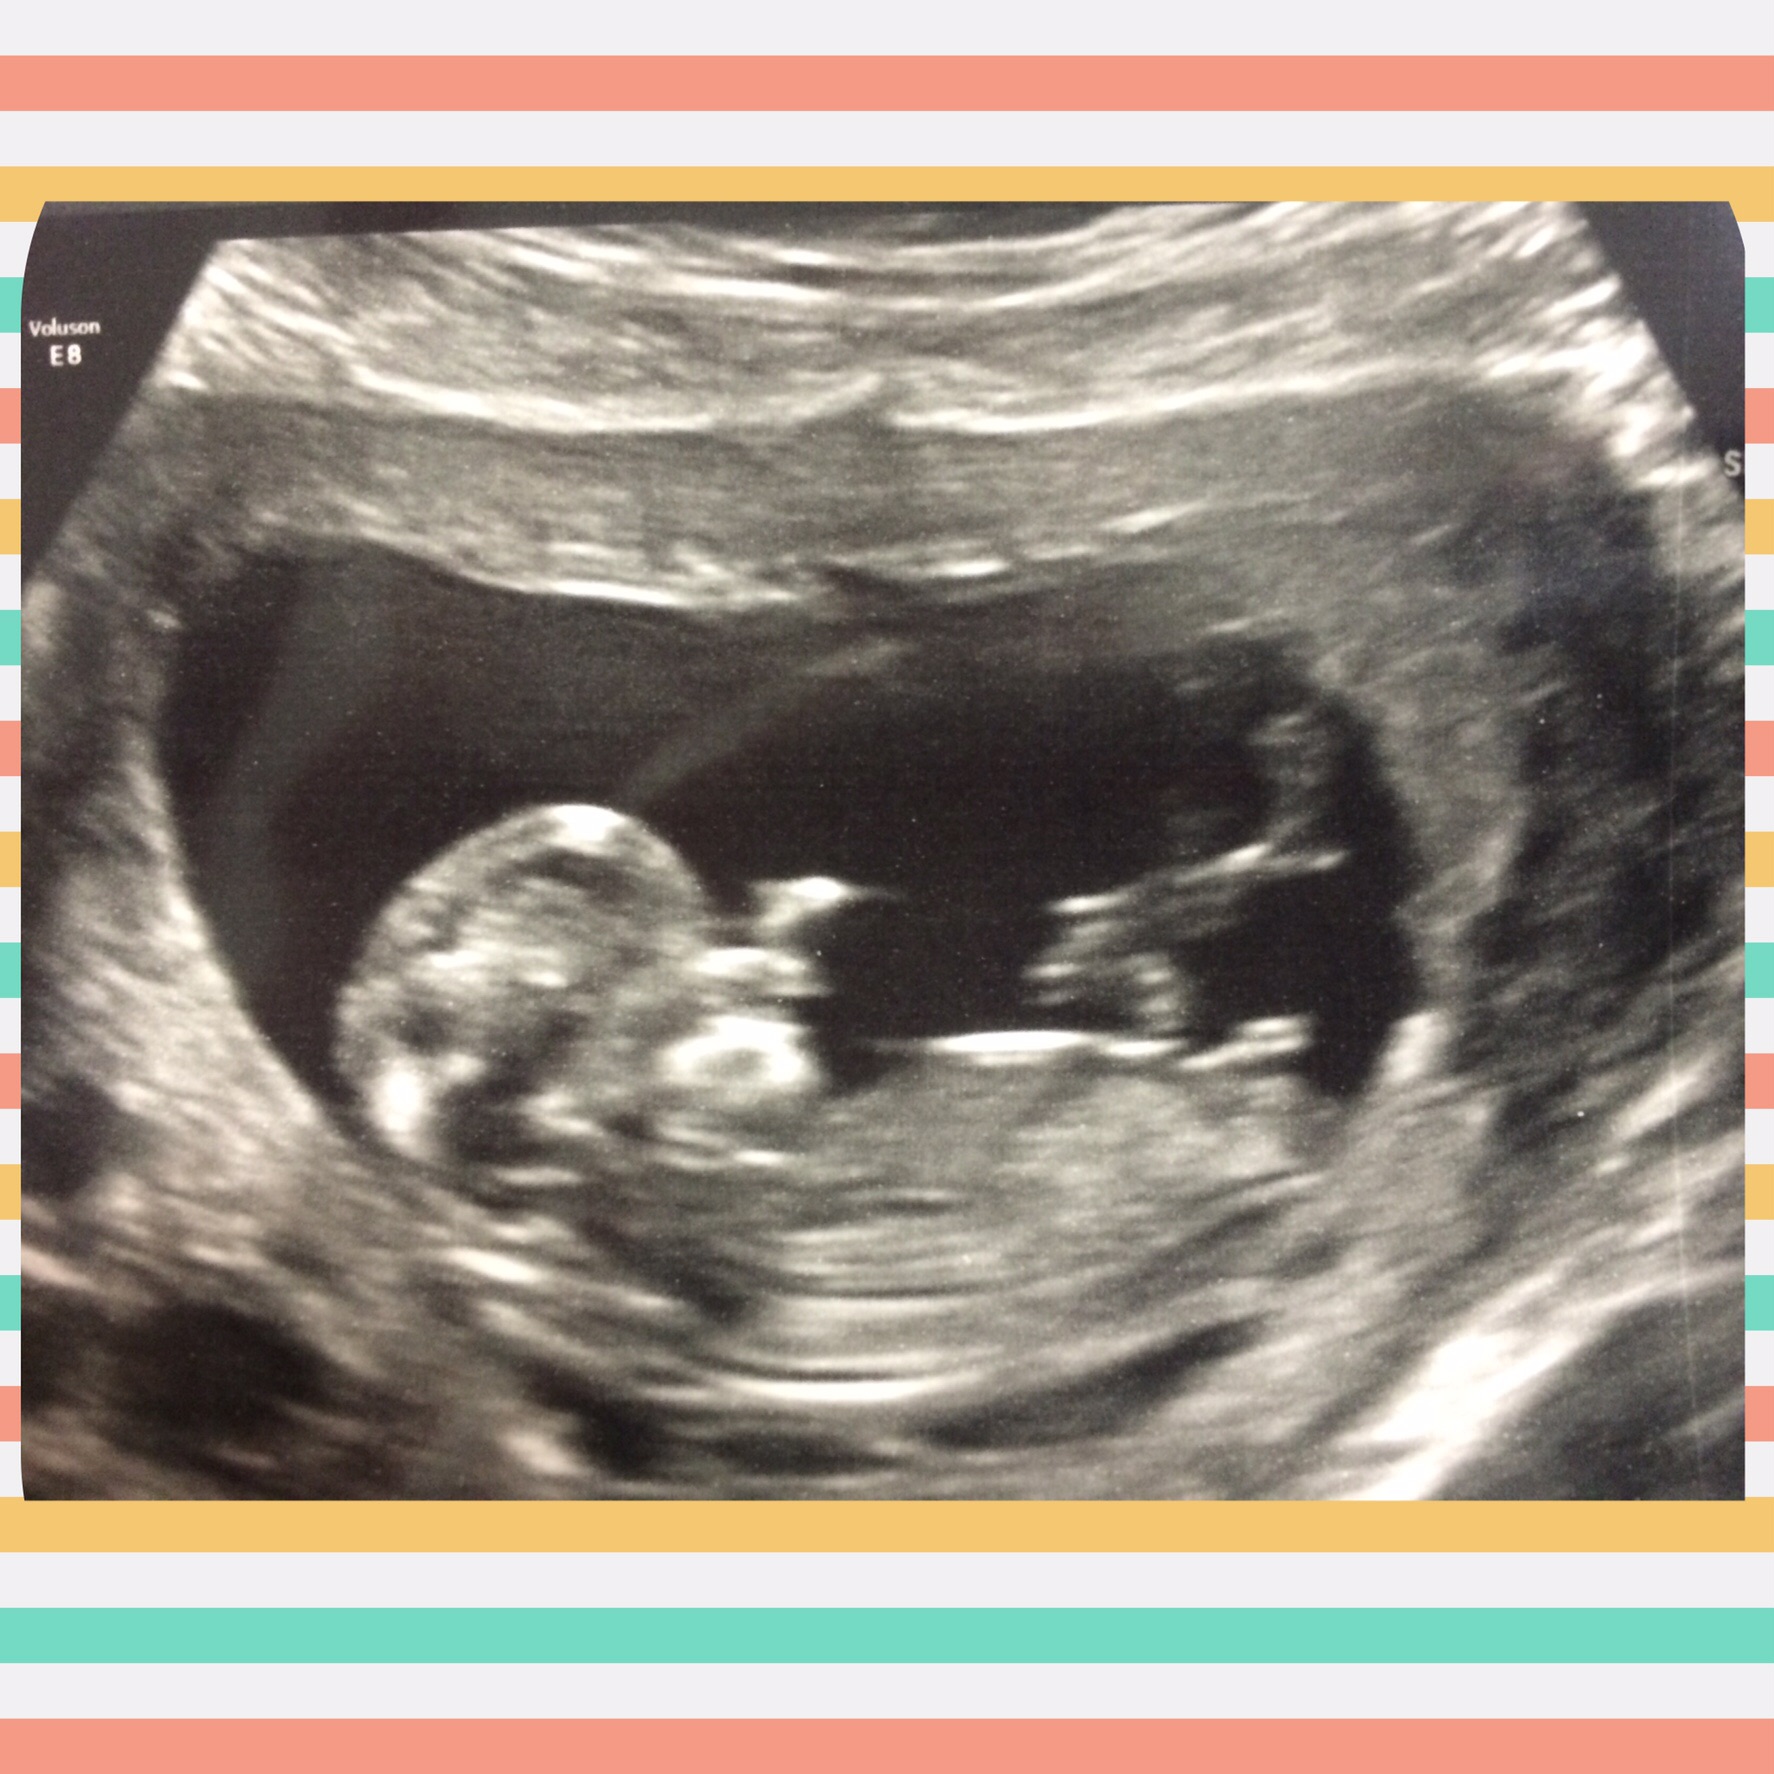

14 weeks, 1 day. I had an abdominal u/s. I've decided to call it my little wiggle worm because it wouldn't stop moving around, and stretching! It took three tries for the tech to capture the heartbeat (148). At one point she managed to get positioned just right to see it's entire front, and not even a second later, it completely turned itself around